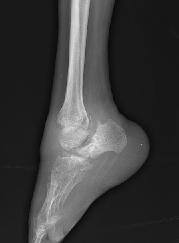

4.末梢自主神經受累表現可導致肢體末端皮膚營養障礙表現為指趾短小脫落骨溶解足穿孔和Charcot關節。麻風周圍神經病為慢性增殖性炎症皮下感覺神經可觸及肥大,以耳大神經和尺神經多見。